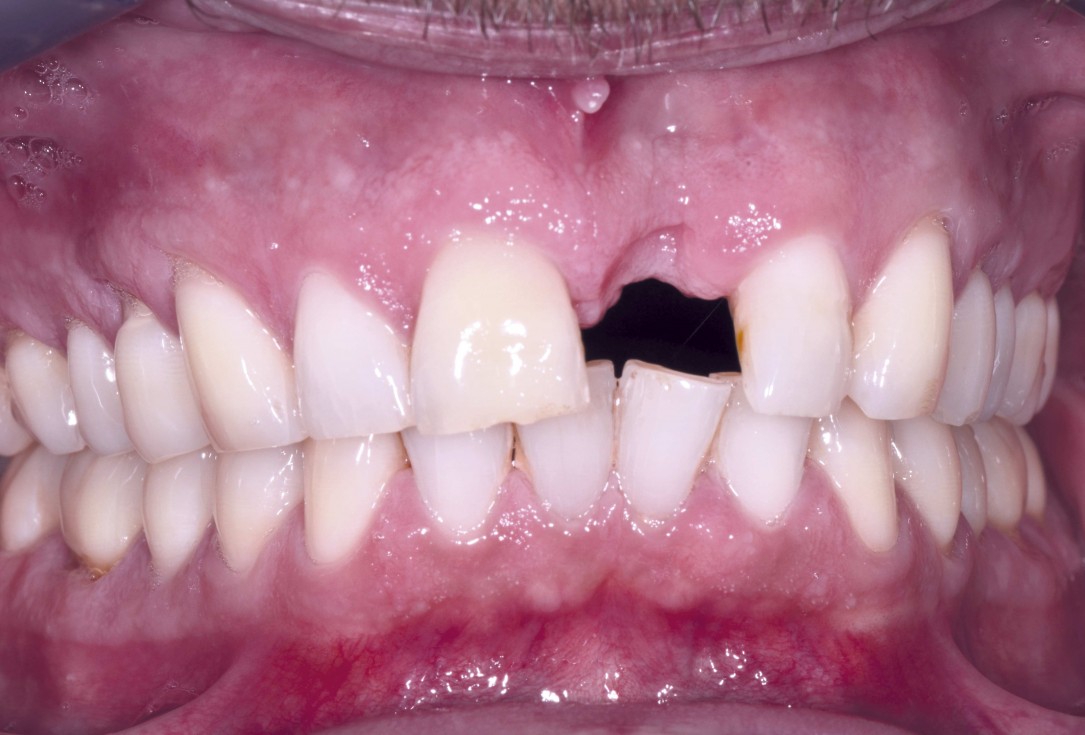

06/18 - Extensive bone defect